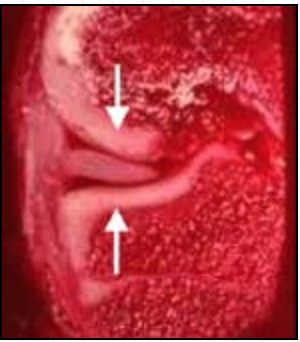

FIGURE 1b

This photograph demonstrates a cross-section of the medial half of a normal human knee specimen. Above, you see the rounded contour of the femoral condyle. Below, you see the flatter, upper surface of the tibia. These two bones have been drawn apart here to better demonstrate the meniscus (see arrows), which lies between them. You can see that the meniscus is a wedge-shaped structure when viewed in cross-section. It is held in place here by its attachment to the knee's capsular ligament on the left-hand side.

FIGURE 1c

In this picture, the same knee anatomy specimen seen in Figure 1-b is shown, but in a more normal anatomic configuration, with the femur (above) resting upon the tibia (below). Here you can easily see how the meniscus serves as a natural cushion or pad, interposed between the femur and tibia. The arrows demonstrate the direction of joint loading forces while standing. This specimen also demonstrates nicely how the bones of the knee are lined with articular (joint surface) cartilage (the white, border tissue coating the spongy-appearing, dark red bone). Articular cartilage adds to the shock-absorbing capability of the knee and provides the joint with smooth, low-friction gliding surfaces.